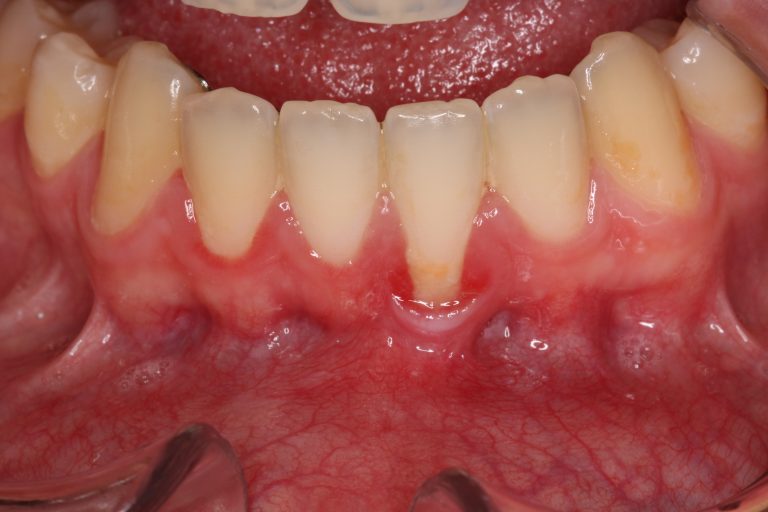

Les greffes réparatrices de gencives. La greffe de gencive est aussi appelée greffe de tissus mous. Elle a pour objectif de réparer la gencive qui présente un déchaussement (récession gingivale). La greffe consiste en l’augmentation d’épaisseur des tissus. Cela permet d’obtenir la stabilité du niveau de la gencive autour de la.. Définition. La greffe de gencive est un acte de parodontologie chirurgicale permettant de greffer du tissu gingival dans le cas d’une rétractation de la gencive (récession de la gencive). Cette greffe a pour pu de corriger le déchaussement des dents, de préserver leurs racines de l’érosion et des caries et de limiter l.

La greffe de gencive libre : cette technique a pour avantage de permettre un gain considérable au niveau de l’épaisseur de la gencive.. On pourra alors envisager une nouvelle greffe 3 à 6 mois après. Il n’y a pas de contre-indications, le palais se régénérant très vite”, conclut-il. Il faut savoir que le recouvrement total n’est pas.. Une greffe de gencive est recommandé pour stabiliser ou améliorer le déchaussement des dents (la récession gingivale). Cette dernière est causée par différents facteurs tels un biotype gingival mince, un mauvais brossage ou un brossage trop fort, le déplacement des dents en orthodontie, des forces occlusales excessives ou la position.